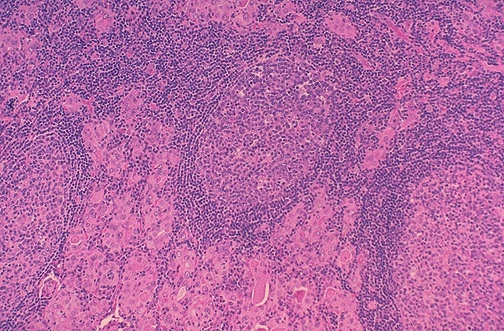

Image 5.3

What changes are present at higher power?